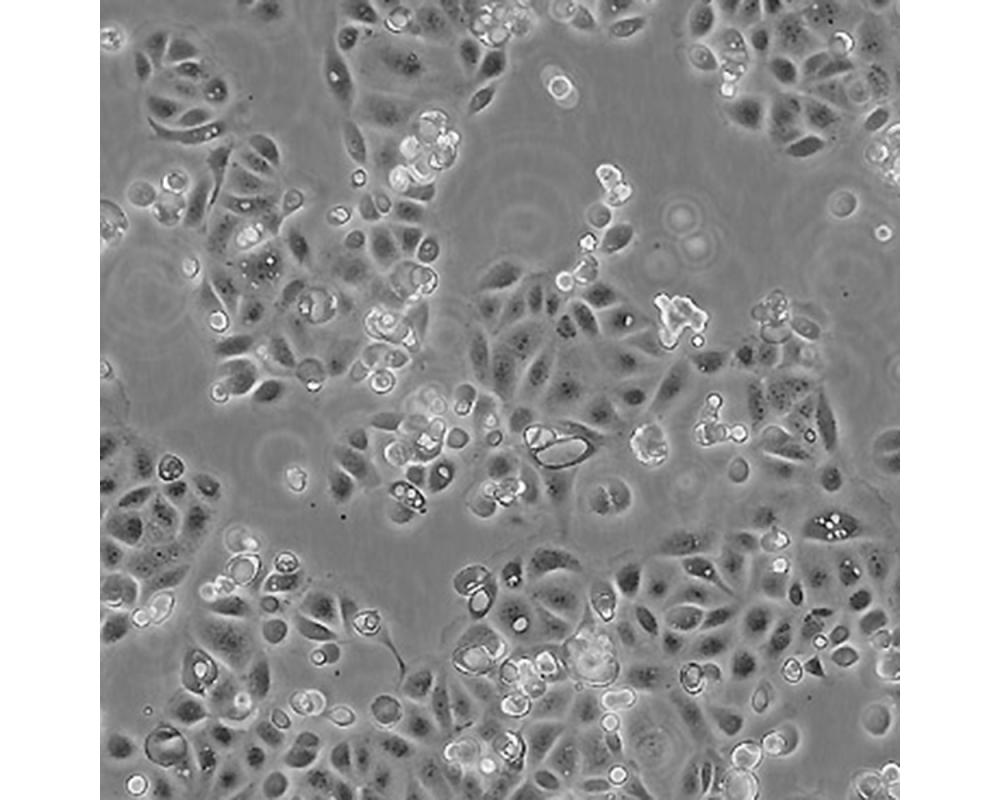

SW1990

產(chǎn)品名稱 SW1990

中文名稱 人胰腺癌細胞

組織來源 胰腺癌;男性

生長特性 貼壁

培養(yǎng)基 L15,90%;FBS,10%;雙抗。

培養(yǎng)條件 Atmosphere: Air, 95%; CO2, 5%。Temperature: 37℃